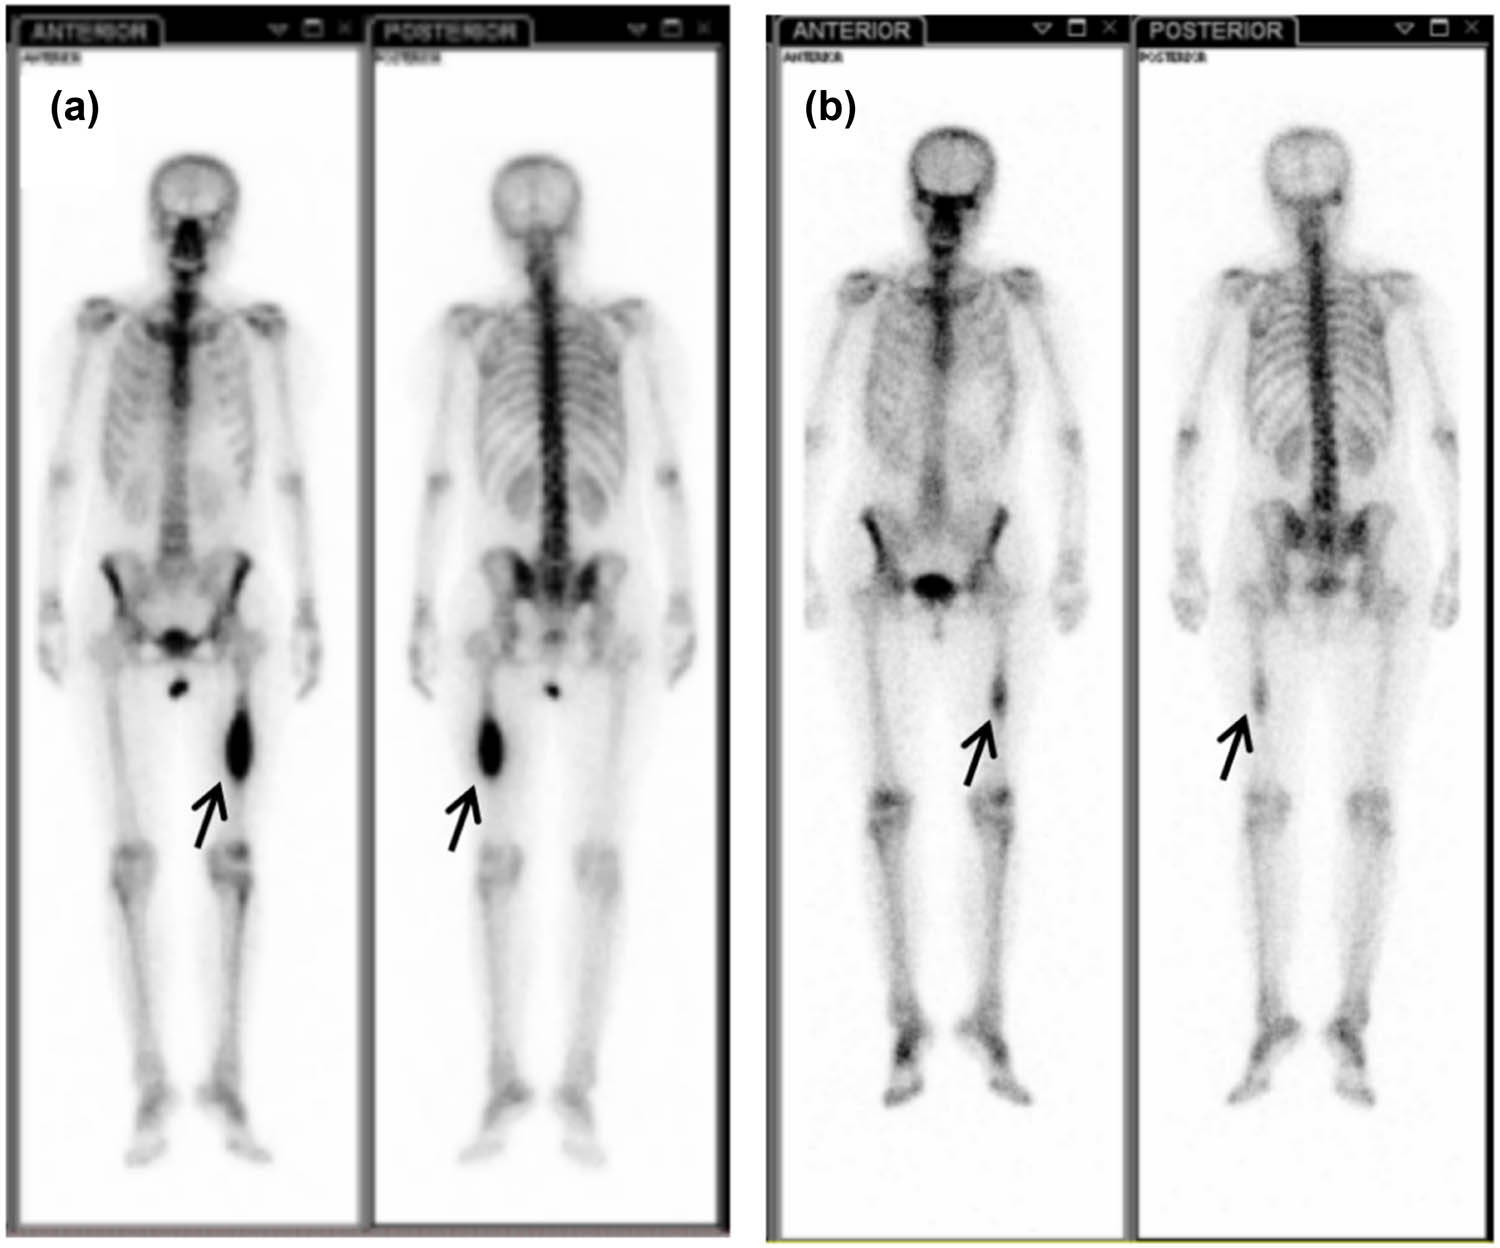

The histology of the pathological changes confirmed by both pleural biopsy (Figure 3a and b) and fiberoptic bronchofiberscopy biopsy (Figure 3c and d) was adenocarcinoma of the lung. Then the EGFR mutation status was investigated and the result showed a point mutation at exon 21 (L858R). One month later, the patient underwent a systemic bone imaging examination, which revealed abnormal bone metabolism in the middle of the left femur (Figure 4a). Bilateral femoral MRI showed bilateral femoral shaft metastatic tumor.

Systemic bone imaging. The metabolic activity of hypermetabolic focus in the middle part of left femur decreased significantly after treatment. (a) At the initial visit and (b) after targeted treatment of gefitinib.

The patient received gefitinib and intermittent zoledronic acid for bone metastases until 20 months, and then MRI showed that BMs which had disappeared and shrunk (Figure 2b and d) after gefitinib were progressing again. The cancer lesions in lungs of the patient were significantly reduced (Figure 1c) after gefitinib and did not progress during the treatment period. Systemic bone imaging showed that the metabolic activity of hypermetabolic lesions in the middle part of the left femur was significantly decreased after gefitinib treatment (Figure 4b) and the patient had never been affected by lower limb discomfort.